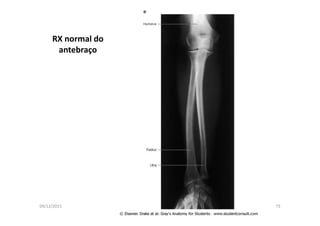

RX normal do

antebraço

09/12/2015 Dr. José Heitor M. Fernandes 74